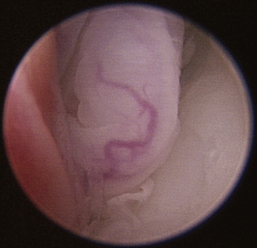

There are many nonspecific changes seen with rhinoscopic evaluation that vary from mild to severe (Figures 19-34 through 19-41). Mucosal hyperplasia, hyperemia, and accumulations of mucoid to mucopurulent secretions are typical findings. Turbinate mucosa can have a classic clubbed and hyperplastic appearance. Progression can result in generalized or polypoid mucosal proliferation or hyperplasia. In severe, chronic cases, infected and necrotic turbinate can be seen. The combination of mucosal hyperplasia and abundant accumulation of mucus compromises the air passageways and can limit the movement of the scope, especially in cats and small dogs. Inflamed tissue bleeds easily and can further decrease visibility. Site selection for biopsy is often nonspecific because most of the nasal mucosa is involved. Bacterial cultures collected at the time of examination may reveal a current secondary bacterial infection, unlikely the primary cause but nonetheless creating pathologic symptoms. Mycoplasma may be of concern in cats with recurring rhinitis.35 Biopsy and appropriate culture submission are critical for developing a specific medical plan to manage the patients’ current symptoms.

image

Figure 19-34 Canine lymphoplasmacytic rhinitis with hyperplasia with turbinate clubbing.

Figure 19-35 Canine lymphoplasmacytic rhinitis with mucosal hyperplasia and turbinate clubbing.